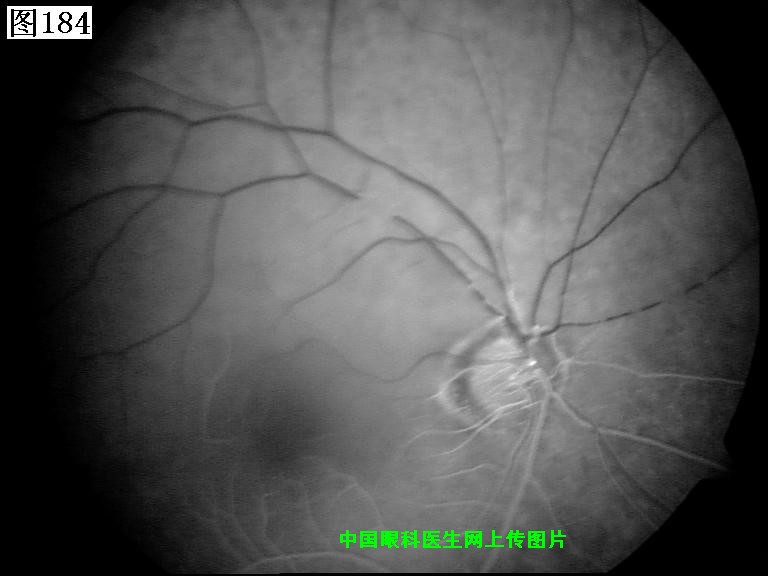

181 182 183 184